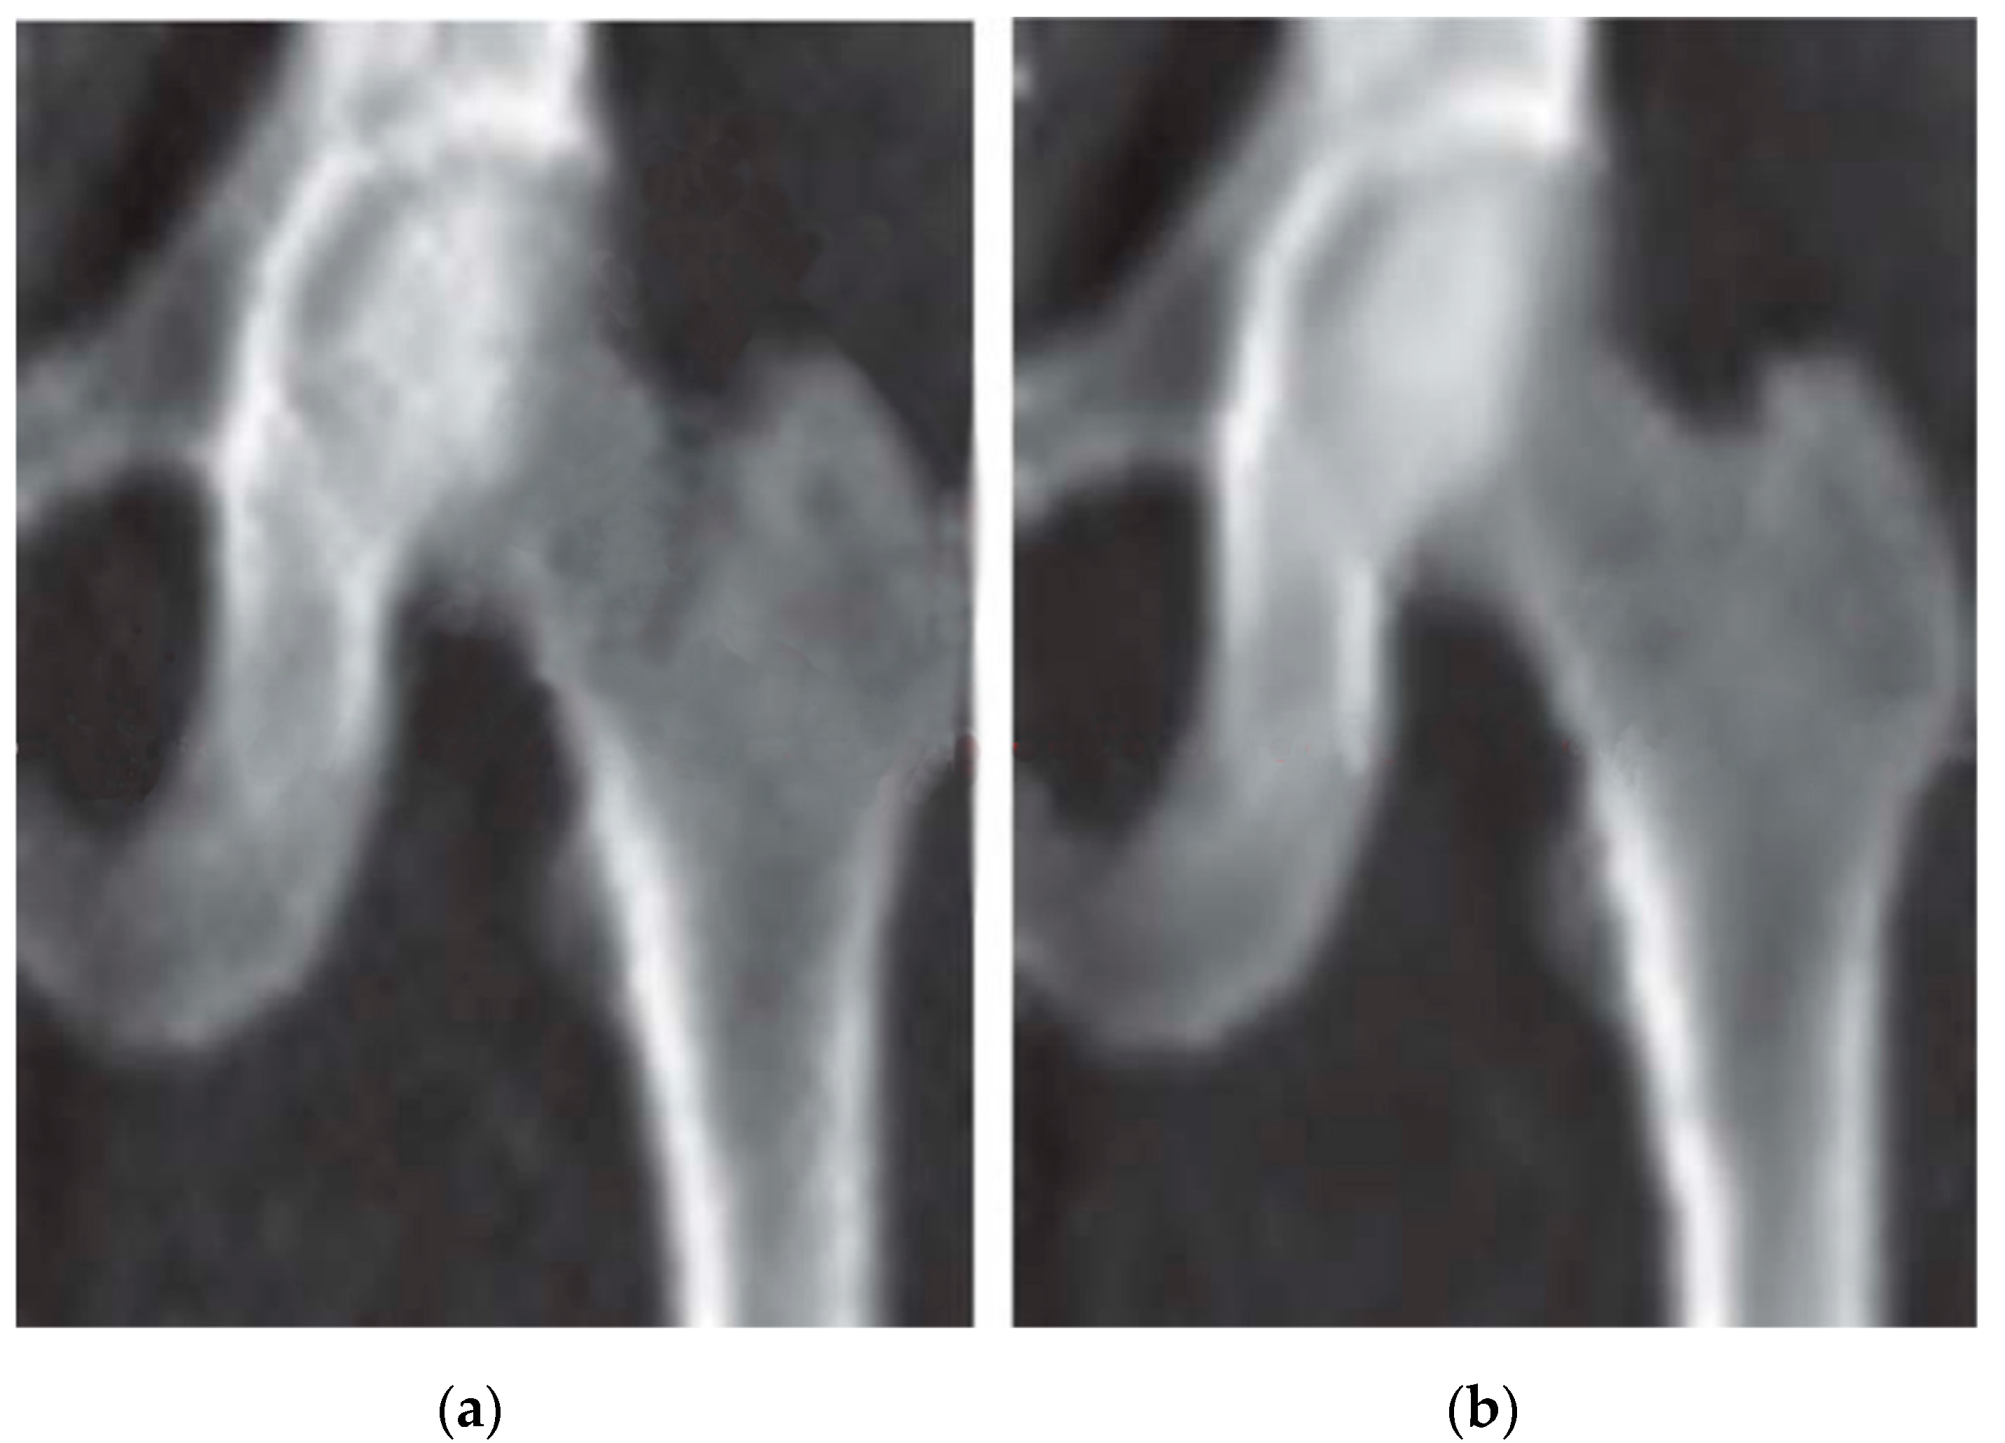

The optimized NLMF was tested and verified with the DXA images of the uniform femur phantom and real human femur images. Preliminary results showed that the signal-to-noise ratio (SNR) for high- and low-energy femur DXA images improved by 15.26% and 13.55%, respectively. Key parameters used include a search window size of 21 × 21 pixels, a patch size of 7 × 7 pixels, and a filtering strength (h) set to 10. Figure 3 shows some of the denoised results of femur DXA images using NLMF. More details about our NLMF work for denoising DXA images are available in references [33,34].

The proposed denoising techniques via NLMF, Gaussian filtering, and wavelet-based methods for DXA images were evaluated experimentally with femur data. The performances of denoising filters was evaluated quantitatively in terms of mean-to-standard deviation ratio (MSR), signal-to-noise ratio (SNR), and contrast-to-noise ratio (CNR). The proposed noise reduction techniques significantly improve the quality of DXA images and image segmentation results, while preserving the fine details of anatomical structures. Compared to other denoising methods, wavelet-based filtering has shown higher performance in the case of the average improvement ratio of MSR, SNR, and CNR and improves the quality of DXA images. Table 1 presents the effects of NLMF, GF, and CWT filters. MSR, or mean-to-standard deviation ratio, quantifies the quality of DXA images by comparing the mean pixel value across the entire image to the standard deviation within a specified region of interest (ROI) of 10 × 10 pixels, as outlined in [34,38,52]. A higher MSR value indicates superior image quality, reflecting clearer and more defined anatomical details. SNR, measured in decibels, was calculated for both original and denoised DXA images. It evaluates the signal strength relative to the noise level, with μo representing the mean pixel value of the bone object and σROIbg denoting the standard deviation in a background ROI of equivalent size. Higher SNR values indicate effective noise reduction and improved image clarity. Similarly, CNR in decibels was estimated to assess the contrast between the bone and background regions, providing insights into the image’s diagnostic utility and overall enhancement achieved through denoising techniques. A sample of original and denoised images with NLMF is shown in Figure 5.

Figure 5. Image denoised with NLMF: (a) original and (b) denoised image.